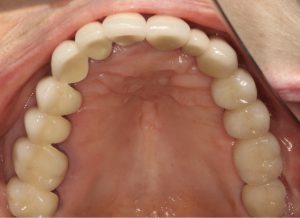

4年前に来院した時には右上、左下のブリッジが脱落し根は残せない状態でした。その後インプラント治療を選択、無事完了。

再度右下3本と、左下1本インプラントを入れて無事治療は終了しました。

そして3ヶ月たった本日。定期検診にいらしていただきました。